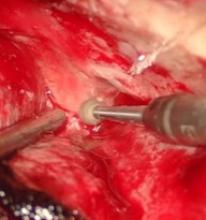

Acute post-surgical pneumocephalus is frequent in patients with cranioencephalic pathology operated on in the supine and prone position. The distribution and degrees of pneumocephalus may be related to sex, the type of cranioencephalic pathology, and the depth of the surgical lesion.